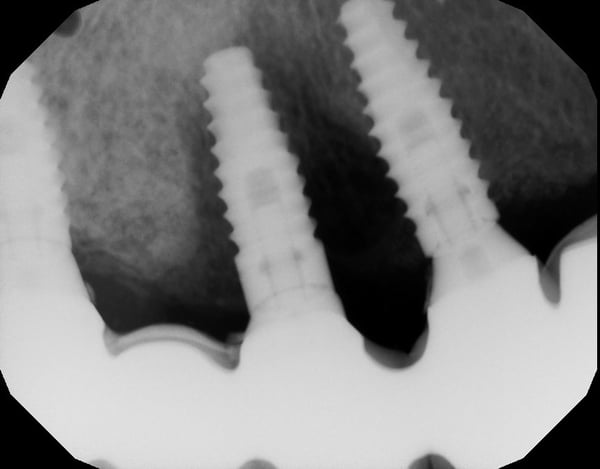

This patient presents with periimplantitis of the lower left quadrant. Removal of existing implants with Guided Bone Regeneration is required. The tent pole technique for GBR was used.